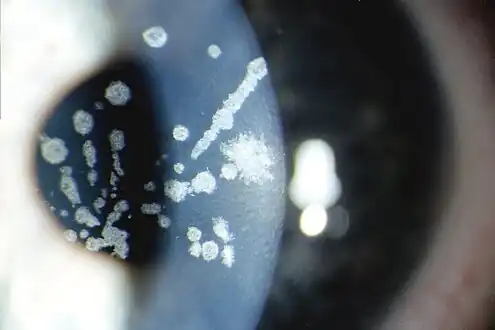

| Granular corneal dystrophy type I, Numerous irregular shaped discrete crumb-like corneal opacities | |

Granular corneal dystrophy is a slowly progressive corneal dystrophy that most often begins in early childhood.

The presentation of Granular corneal dystrophy includes glare and photophobia that usually begin prior to the age of 10 y.o. Visual acuity declines as opacification advances with age.[4]

Granular corneal dystrophy is diagnosed during an eye examination . The lesions consist of central, fine, whitish granular lesions in the cornea. Visual acuity is slightly reduced.[4]